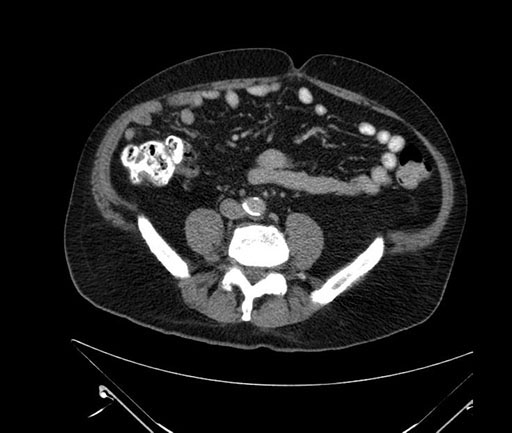

Imaging Analysis

Look through the patient's CT scan to identify any areas of concern for the necessary procedure.

Based on your CT findings, which issue(s) would give reason for "planned slowing down moment(s)" in this case?